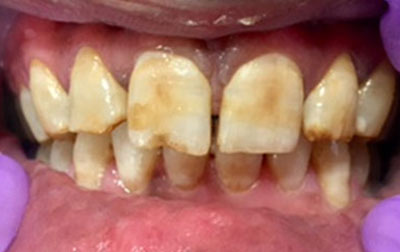

Laminates:

Dental laminates closely resemble dental veneers and are becoming a preferred choice for enhancing smiles. Available in composite or porcelain, these thin, customized shells offer numerous advantages. They effectively mask stains and discolorations on individual teeth, especially when conventional teeth-whitening methods fall short. In cases of stubborn and deep dental stains caused by factors like excessive fluoride or certain medications, standard whitening procedures often prove ineffective. Dental laminates step in as a promising solution, especially with lighter-colored variants effectively concealing teeth with severe discoloration.

Beyond staining, laminates address unexpected dental issues such as chips, wear, or breakage. They swiftly camouflage imperfections, whether on a single tooth or multiple ones, revitalizing the overall dental aesthetic. Dental laminates also serve as a corrective measure for uneven, misaligned teeth, as well as indentations and protrusions. A minor enamel trim enhances the adherence of these thin shells while preventing overcrowding and closing gaps between teeth. With the ability to seamlessly match natural tooth shades, dental laminates seamlessly integrate into the oral environment. Patients even have the flexibility to select their desired level of tooth whiteness.

Notably, the effects of dental laminates are enduring, eliminating the need for subsequent adjustments or reshaping. In essence, dental laminates offer a versatile and lasting solution for an array of dental imperfections, yielding confident smiles without the constraints of staining, damage, or misalignment.